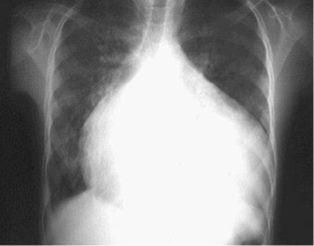

Derrame pericárdico

60% de los casos.

Ruidos cardiacos suelen debilitarse.

Desvanecimiento del impulso de la punta.

Aumento del tamaño cardiaco.